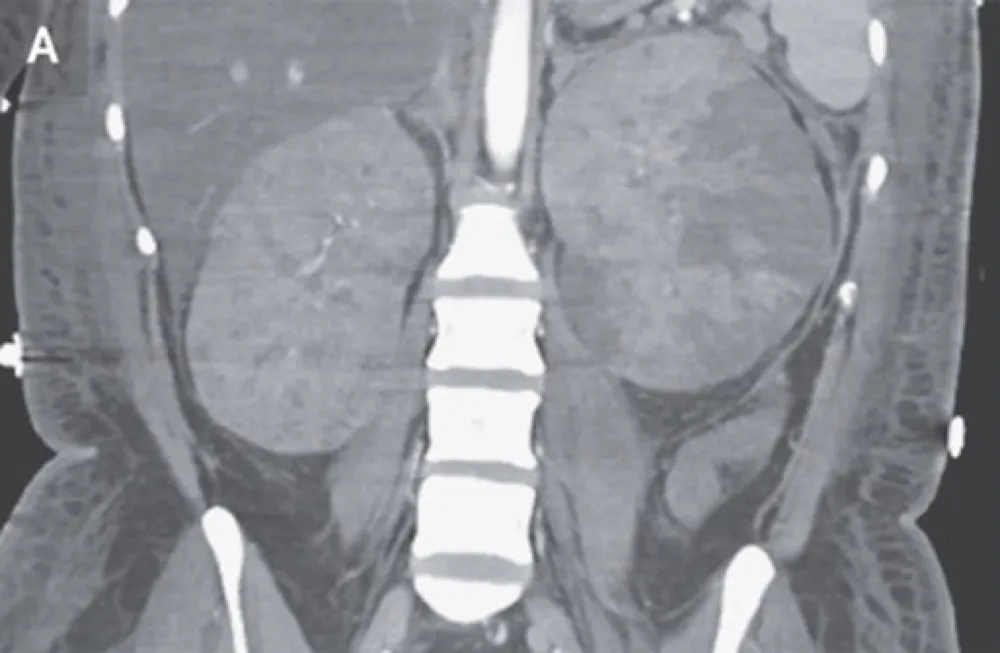

Diante de pacientes com múltiplos tumores de células renais claras devemos pensar na possibilidade de doença de Von-Hippel Lindau. O tratamento visando poupar massa renal pode fazer muita diferença

Valkercyo Feitosa

3 anos atrás